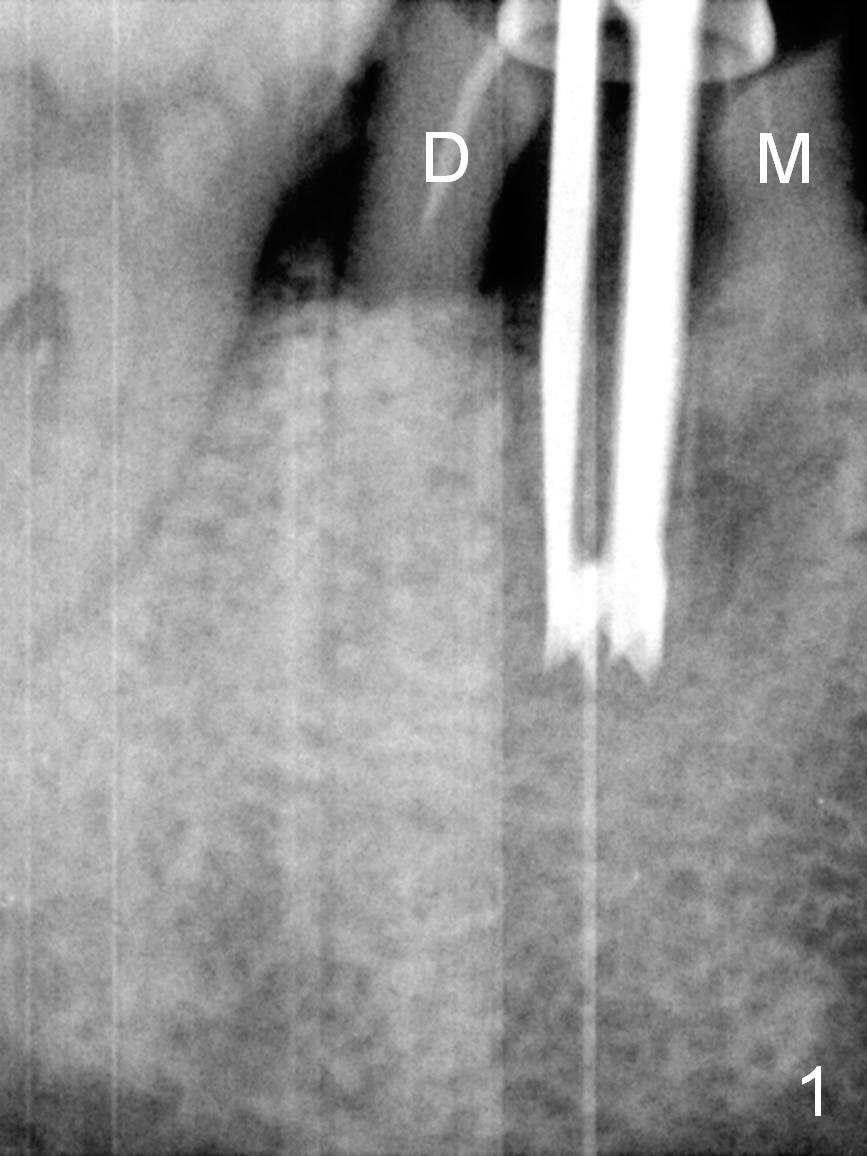

After cleaning the root surface with a surgical curette, a 1.6 mm pilot drill is used to start osteotomy (O) between the mesial (M) and distal (D) roots, followed by a marking bur and 3.8 mm Magic drill 13 mm deep (Fig.1,2). Following root removal, the 3.8 mm drill is reused for 11 mm (Fig.3). After deepening the osteotomy for another 2 mm, a 4.5x13 mm implant is placed with insertion torque of 50 Ncm, followed by allograft (*, .5-2 mm) and a 5x4(2) mm abutment (Fig.4,5). An immediate provisional is fabricated to close the socket (Fig.6 P (lock in)). The detached buccal gingiva (Fig.6 *) is kept in place by applying periodontal dressing (Fig.7 *). Red dashed lines in Fig.1, 3, 5 represents the superior border of the Inferior Alveolar Canal and Mental Foramen.